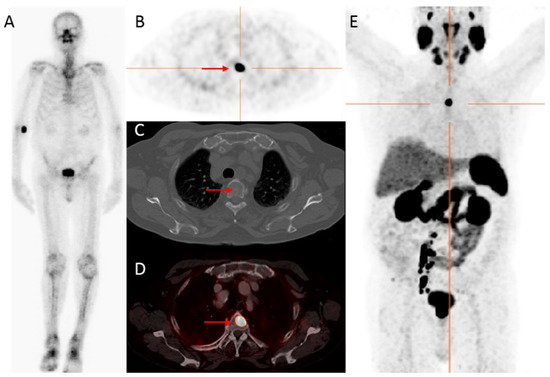

Figure 2.

Initial assessment of a 75-year old patient, newly diagnosed with PCa (Grade Group (GG) 5), with an initial PSA-value of 1396 ng/mL. On bone scintigraphy, the increased uptake in the thoracic spine was attributed to an (osteoporotic) collapsed vertebra, and the faint uptake in the left third rib to a post-traumatic origin. Despite the high PSA-value, no abnormal uptake consistent with osseous metastases was visualized (A). However, extensive metastatic disease was found on 18F-DCFPyL PET/CT (B–E). For example, transversal 18F-DCFPyL PET (B) and fused PET/CT (D) showed highly increased PSMA-expression in the right iliac bone (red arrow, maximum standardized uptake value (SUVmax) 8.15), compatible with a lytic lesion on CT (C). The time interval between bone scintigraphy and 18F-DCFPyL PET/CT was 5 days.